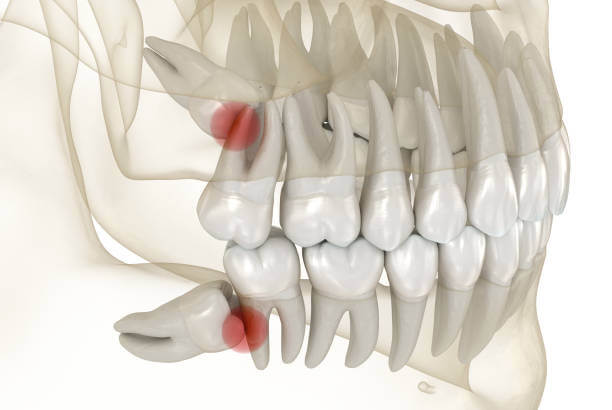

인류의 턱이 작아지면서 입안 깊숙이 사랑니가 자랄 공간이 부족해졌고 이 때문에 사랑니는 눕거나 발치하는 등 썩거나 염증이 생기기 쉬운 모양으로 나오는 경우가 많습니다.

사랑니는 다른 치아에 비해 크기와 모양이 매우 다양합니다. 사랑니는 똑바로 나오지 않고 기울어져 있거나 누워있는 경우 잇몸에 묻혀 있는 부분이 많습니다.